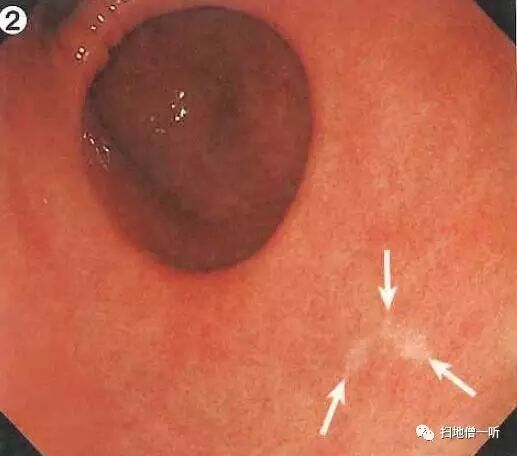

A:胃癌在图2。HP未感染胃癌。

整体胃粘膜光滑,未见明确萎缩。白光下可见无数小红点规则排列(RAC),所见为HP未感染征像。

接近观察及NBI非放大观察可见粘膜呈退色调改变,靛胭脂染色后界限不清。未分化癌初期可呈IIb表现,随着肿瘤进展可出现凹陷。本院数据显示当肿瘤小于10mm时 IIb36%,IIc64%;肿瘤11mm-20mm时 IIb6%,IIc94%

最终诊断:胃窦前壁,O-IIb,3mm,sig,T1a(M),UL(-)

小结:RAC提示HP阴性

HP阴性需要注意寻找未分化癌

未分化癌以退色调多见

初期未分化癌可只出现色调变化而不伴随凸凹变化